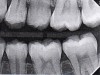

Fig 12. Six-month results of SDF proximal surface saturation in a teenaged patient. As seen in pretreatment bitewing film (Fig 12) and 6-month post-SDF bitewing films (Fig 13 and Fig 14), proximal radiolucencies appeared unchanged while some improved.

Figure 12

Fig 13. Six-month results of SDF proximal surface saturation in a teenaged patient. As seen in pretreatment bitewing film (Fig 12) and 6-month post-SDF bitewing films (Fig 13 and Fig 14), proximal radiolucencies appeared unchanged while some improved.

Figure 13

Fig 14. Six-month results of SDF proximal surface saturation in a teenaged patient. As seen in pretreatment bitewing film (Fig 12) and 6-month post-SDF bitewing films (Fig 13 and Fig 14), proximal radiolucencies appeared unchanged while some improved.

Figure 14

The senior author's (TPC) private practice experience with soft-tip insertion of SDF into contacting proximal surfaces of teeth is that most beginning proximal surface caries lesions cease to progress, as evidenced by subsequent bitewing radiographic comparisons (Figure 3 through Figure 6, Figure 12 through Figure 18). The chances for success vary, however, depending on frequency of application, subsequent flossing by patients or adults flossing younger children, diet control, individual mouth chemistries, and use of fluorides for the topical effect. It must also be emphasized that office staff should make extensive efforts to inform children and parents that subsequent daily flossing is needed to accompany SDF treatments; otherwise, SDF applications will only delay the inevitable progression of caries. Flossing methods should be demonstrated for patients and for parents so they may see how to floss younger children. Showing them enlarged graphic photographs of flossing results may be helpful in this regard. Parents and patients should be made aware that if interproximal dental plaque accumulations persist without daily interruption by flossing, the acid insult will eventually take its toll on the proximal surfaces and caries lesions will progress to the point where restorative intervention may be required.